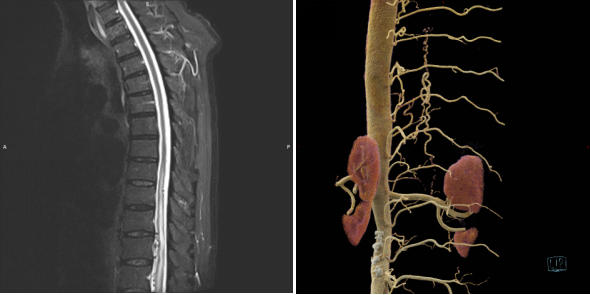

• 神经外科手术计划软件

• 神经外科手术实时导航系统